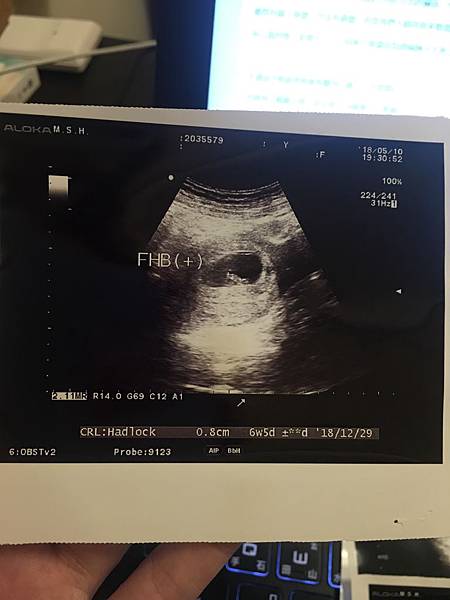

因為有聽說最好要等到小紅過期一個多禮拜再去看醫生照超音波會比較看得見,

所以雖然很早就驗出兩條線了,但我們還是等了一小段時間才去照超音波。

Sandra❤ 發表在 痞客邦 留言(0) 人氣(416)